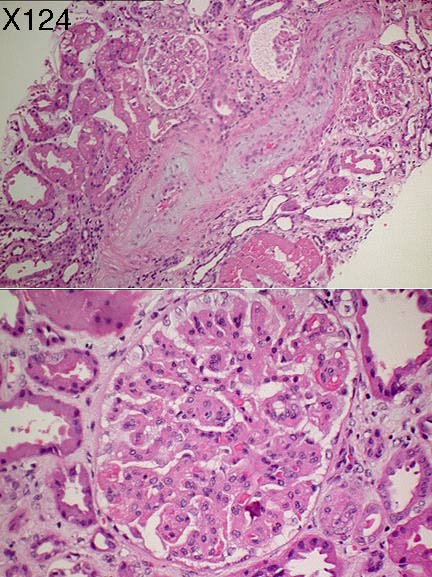

Фотографии медицинских исследований инсулиномы и синдрома Триады Уиппла